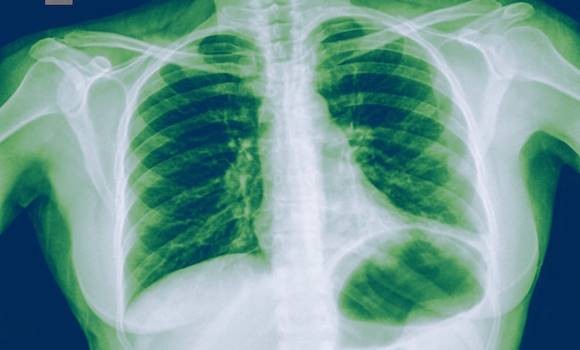

The onset of pneumonia can have different causes. Most often the triggers are viruses or bacteria. Unfortunately, physical-chemical influences can also cause pneumonia. Such an illness can even be life-threatening. How can it be identified in time?

Pneumonia is particularly dangerous in young children, people with chronically impaired immune systems, and in seniors. Pneumonia is an inflammatory disease affecting lung tissue. The most common causes of the disease are bacteria, viruses, fungi, and various parasites, which are otherwise considered infectious agents. This is in contrast to pneumonia caused by physical-chemical particles. These compounds are not infectious, so you will not infect another person. In such cases the course is milder and death only very rarely occurs. The bacteria that cause a severe course of pneumonia are: Haemophilus influenzae, Staphylococcus aureus and Streptococcus pneumoniae. These bacteria are the main triggers that cause health problems. This is mainly because bacterial pneumonia is not recognized early on.